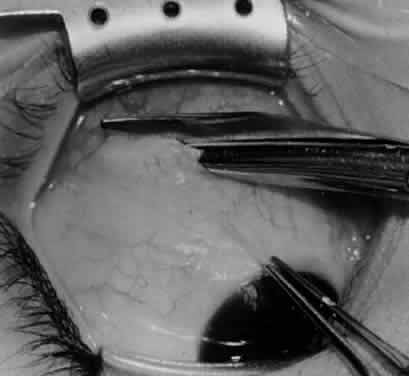

Fig. 14. The inferior temporal vortex vein, 8 mm posterior to the temporal insertion of the inferior rectus muscle, is held on a Green muscle hook.

Fig. 15. The placement of sutures within the sclera for a recession procedure of 10 mm. The anterior suture is placed 3 mm temporal and 2 mm posterior to the lateral insertion of the inferior rectus muscle, and the posterior suture is placed 3 mm further posteriorly.

Fig. 16. Two sutures straddle the inferior temporal vortex vein insertion for a 14-mm recession procedure.